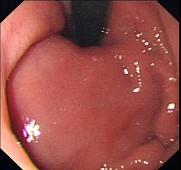

问题 患者,女性,30岁,上腹不适2周,查体:心肺腹未见异常。电子胃镜图片如下,病变部免疫组化CD117阳性,SMA阴性,VIM阳性,诊断为 ( )

选项 A.胃底息肉 B.胃体息肉 C.胃底平滑肌瘤 D.胃体平滑肌瘤 E.胃底间质瘤

答案 E